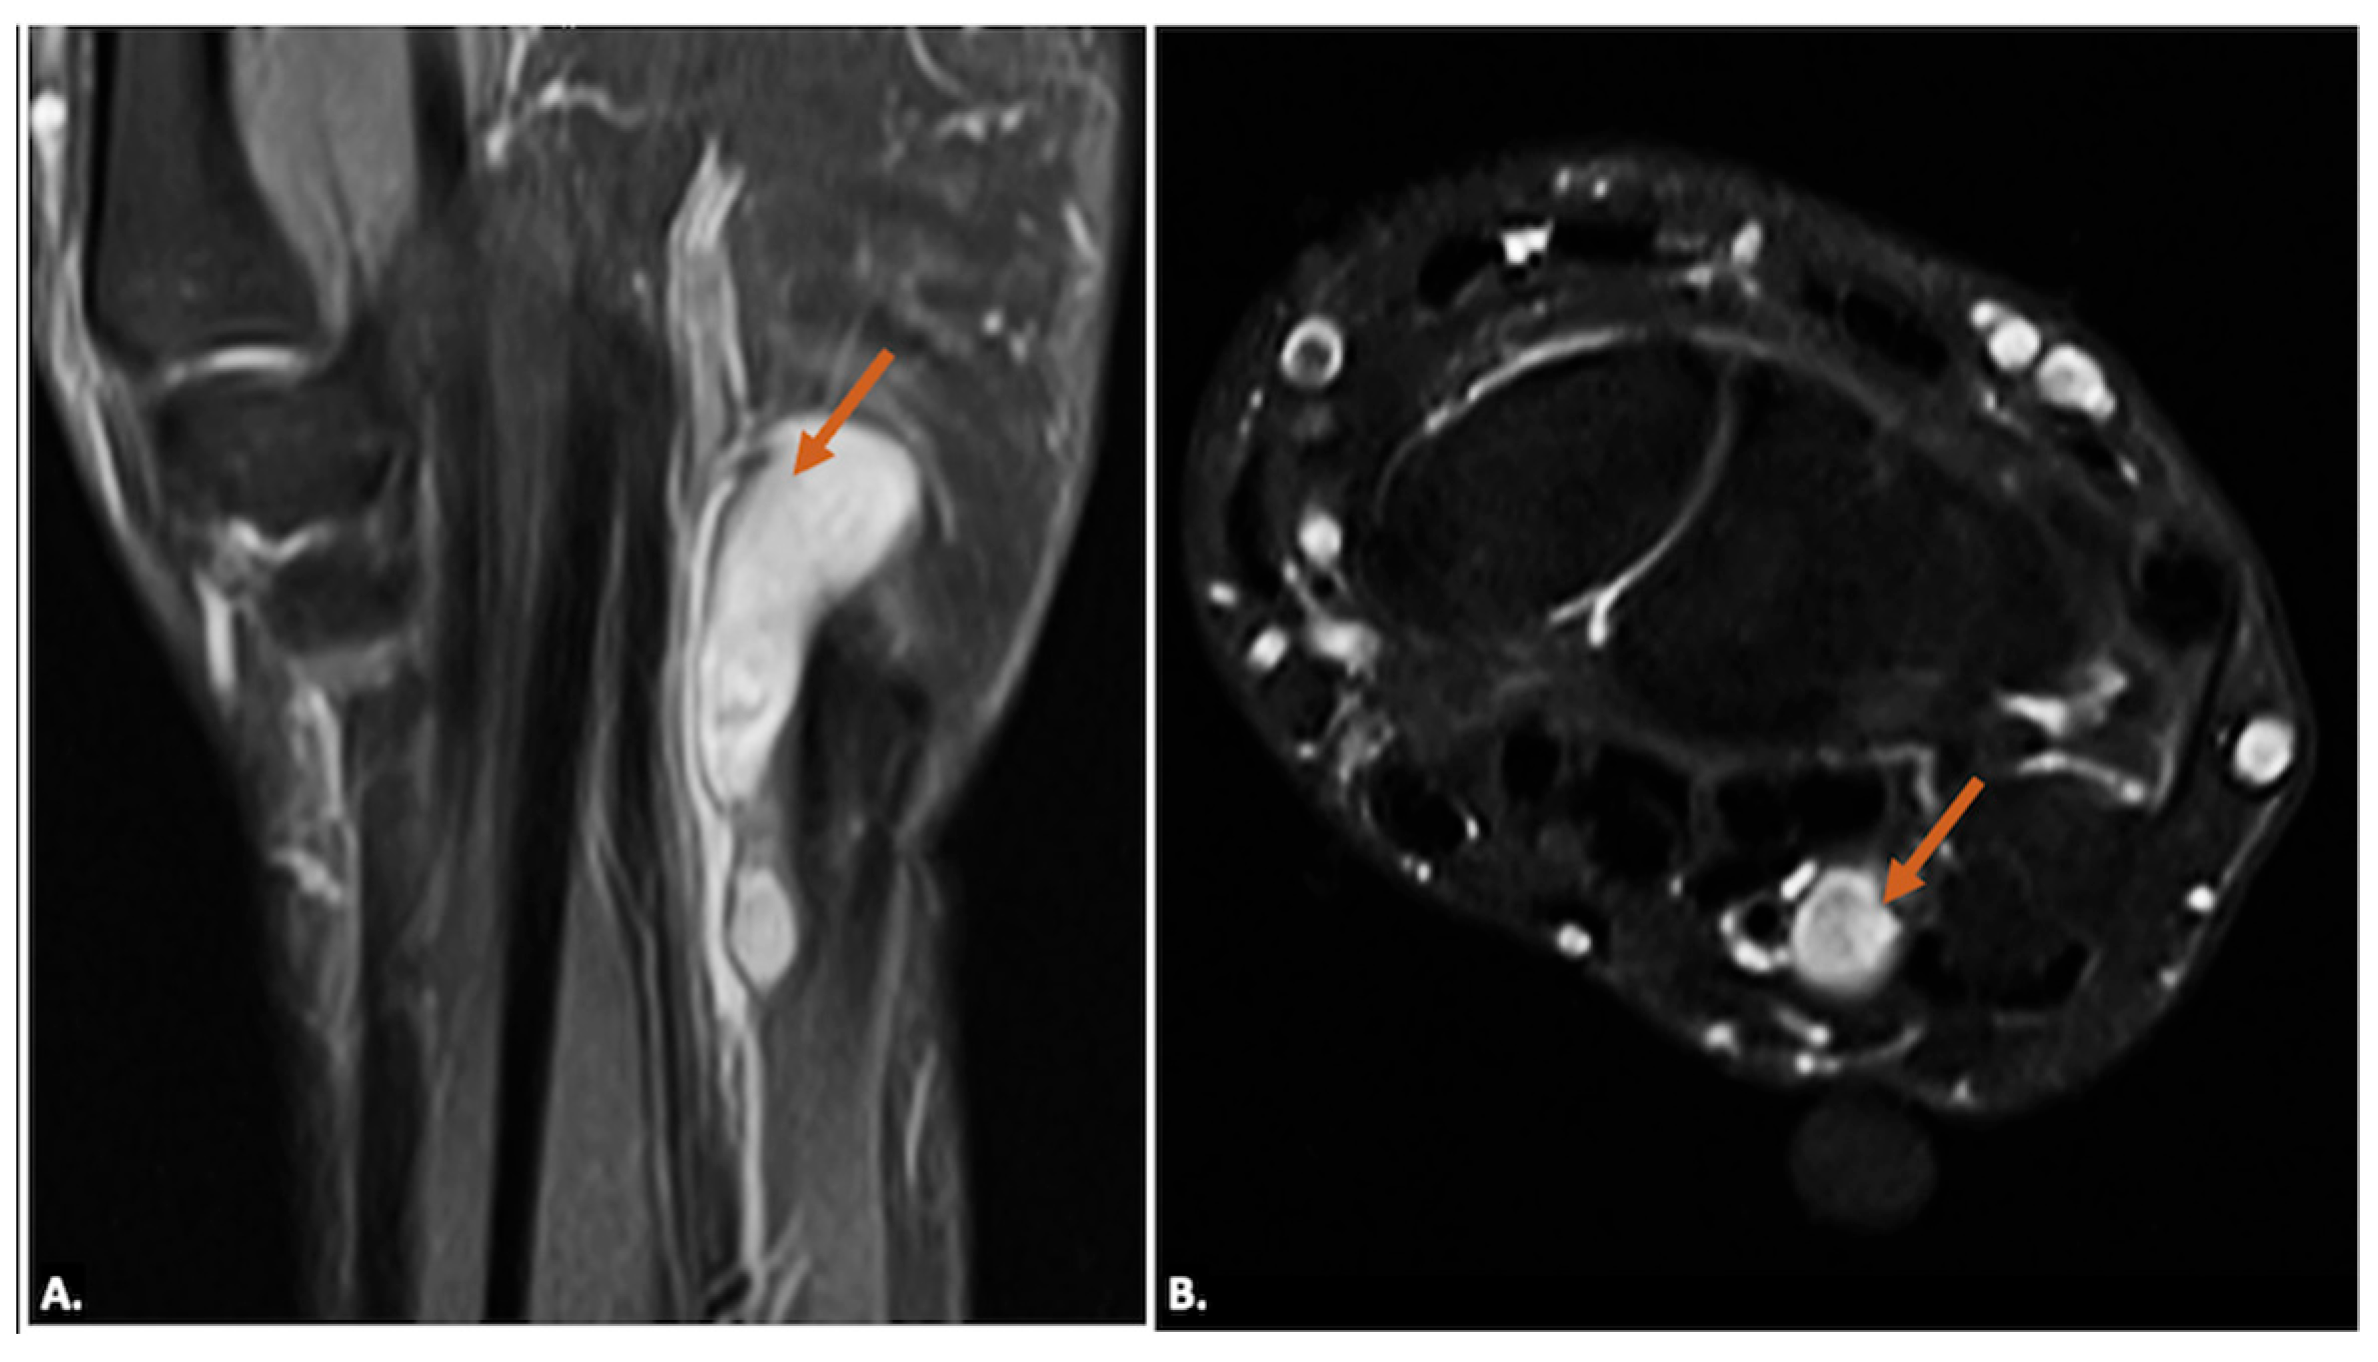

Tenosynovial giant-cell tumours generally arise in relation to the synovial sheath of the tendons or from the synovial lining of the joint. They appear as solid, hypoechoic masses on ultrasound imaging, and the lesions may show well-defined or ill-defined margins. On MRI, they typically appear as low-to-intermediate signal intensity on T1- and T2-weighted images due to hemosiderin deposition and may show blooming on gradient-echo sequences. Post-contrast images reveal variable enhancement (Figure 11). Neurogenic tumours appear as well-defined, hypoechoic masses along the nerve. Doppler imaging may show internal vascularity. On MRI, these lesions are isointense to hypointense on T1-weighted images and hyperintense on T2-weighted images, with a variable presence of “target” appearance on T2, and may show heterogeneous enhancement (Figure 12). The lesions are seen along the course of the ulnar nerve, with the nerve entering into and exiting from it [19].

Figure 11.

(A) Gray-scale Axial Ultrasound image showing a well-defined hypoechoic lesion in the region of Guyon’s canal (indicated by callipers). (B) T1-weighted and (C) T2-weighted axial MR images of the same case showing a well-defined lobulated lesion (arrow) appearing iso-to-hypointense to muscle on both (B) T1-weighted and (C) T2-weighted axial MR sequences in keeping with a tenosynovial giant-cell tumour.

Figure 12.

(A) T2-weighted, fat-suppressed coronal and (B) T2-weighted, fat-suppressed axial MR images of a neurogenic tumour showing a well-defined elongated lesion (arrow) along the course of the ulnar nerve appearing hyperintense on T2-weighted, fat-suppressed coronal (A) and demonstrating ‘Target-Sign’ with central hypointense signal on axial T2-weighted, fat-suppressed (B) sequences.